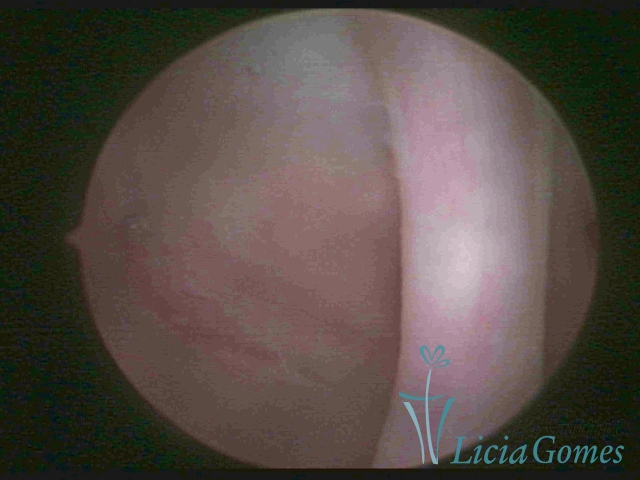

Septate uterus

It probably occurs by the lack of resorption on the middle line, in the merge of Müllerian ducts. The uterus is divided by a partial or total septum which is viewed as a crossbar, not covered by endometrium, which not bleeds when sectioned.

Complete septum when it occupies the whole extension of the cavity, dividing it into two hemicavities.

When this septum occupies only a part of the extension of the uterine cavity, it is considered as incomplete.